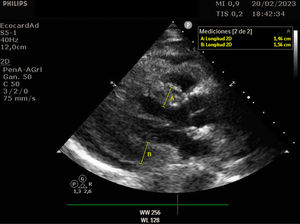

Se trata de una mujer de 41 años con deficiencia humoral y gammapatía monoclonal IgG lambda, que acude al servicio de Urgencias con fiebre y debilidad, siendo diagnosticada de infección respiratoria secundaria a Influenzae A. Veinticuatro horas después ingresa en el servicio de Medicina Intensiva por hipotensión severa, con necesidad de noradrenalina hasta 0,5 ug/kg/min, hipoalbuminemia y hemoconcentración. Se estableció el diagnóstico de síndrome de fuga capilar sistémica con edema intramiocárdico. El síndrome de fuga capilar sistémica es una condición caracterizada por la fuga de plasma y proteínas al compartimento intersticial, y se asocia con gammapatía monoclonal y frecuentemente aparece después de una infección del tracto respiratorio superior, siendo el edema intramiocárdico una complicación poco frecuente. En nuestra paciente, se realizó un ecocardiograma transtorácico al ingreso, mostrando una función ventricular sistólica dentro del límite inferior de la normalidad (FEVI 50-55%), con comportamiento restrictivo, además se evidencia un engrosamiento difuso del miocardio: eje largo paraesternal (fig. 1 y vídeo A), eje corto paraesternal a nivel apical (fig. 2), y plano apical cuatro cámaras (fig. 3), probablemente secundario a edema intramiocárdico, ya que un ecocardiograma transtorácico realizado 1 mes antes mostró grosores normales, eje largo paraesternal (fig. 4). Se prescribió tratamiento con inmunoglobulinas y corticosteroides, pero lamentablemente la paciente falleció 24 horas después del ingreso debido a un shock refractario.